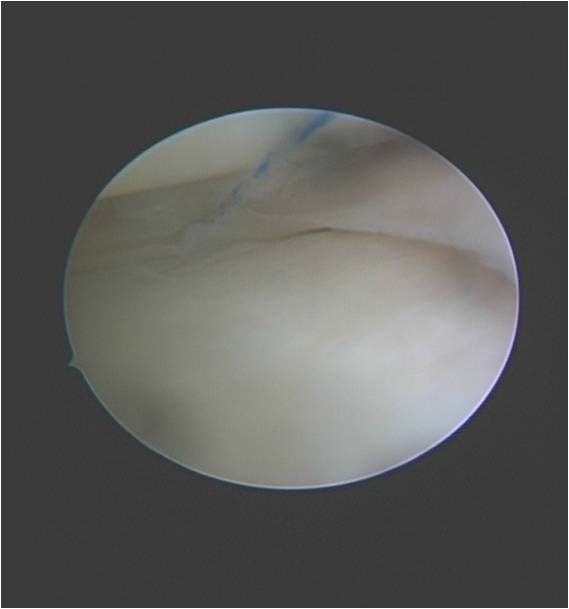

髋关节镜手术